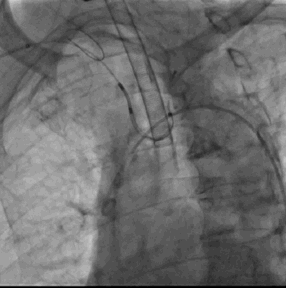

5. 超声及造影下见封堵器放置位置良好,二尖瓣及肺静脉段未见影响,测试位置固定后释放封堵器

6. Sentinel CPS系统